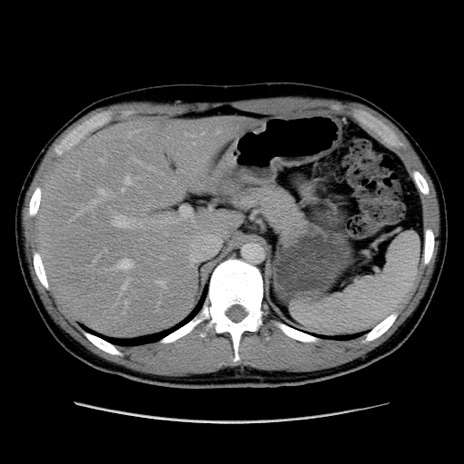

冠状断像

【症例】20歳代 男性

【主訴】心窩部痛

【現病歴】今朝より上腹部痛あり。一旦軽快していたが再度出現したため救急要請。昨日夕に白身の魚を含む刺身を食べた。

【身体所見】BP 136/89mmHg、HR 74/min、BT 37.0℃、腹部:膨満、軟、心窩部に圧痛あり。反跳痛なし、筋性防御なし、腸雑音やや亢進あり。

【データ】WBC 17700、CRP 0.48